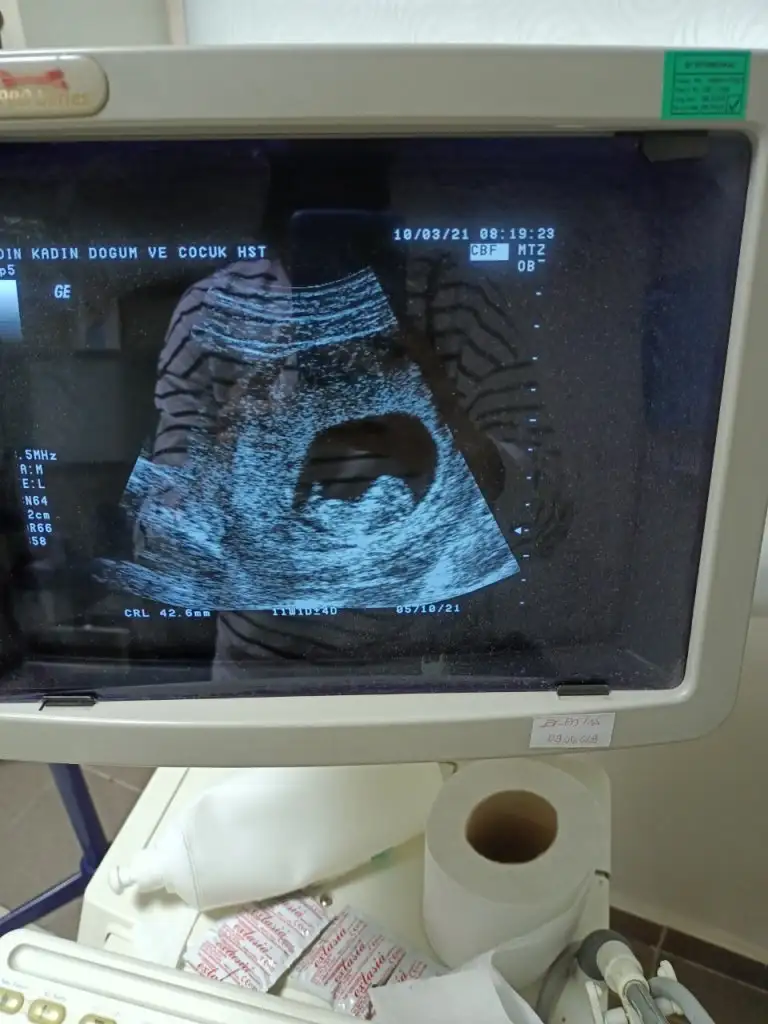

Heyecanla cevabını bekliyoruzMerhabaIkra meyra benim de bebeğimin fotoğrafı bu şekilde. 11+4 deyiz :) doktor göremedim ama acaba nubunu görebilir misiniz?

Erkek sanki 12-13 olursa paylaşınMerhabaIkra meyra benim de bebeğimin fotoğrafı bu şekilde. 11+4 deyiz :) doktor göremedim ama acaba nubunu görebilir misiniz?

Kız gibi sanki emin olamadım13 haftalık cinsiyet tahmini yapabilir misiniz?Ikra meyra

USG yarım almis Dr11+3 bebeğimin ultrason görüntüsüIkra meyra tahmin edebilir misiniz